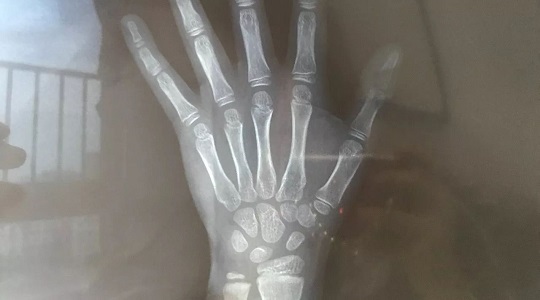

我家小伙子最終被預(yù)測出將來個子可能在174CM左右。這個數(shù)據(jù)是醫(yī)生根據(jù)“年齡身高”、“骨齡身高”、“遺傳身高”以及“體重”等多方因素綜合得出的。

從下圖右邊的橫向柱狀圖可以看出,我兒子的“年齡身高”最加分,也就是9歲男孩139這個身高在全國孩子中處于70%以上水準。骨齡拍出的片子顯示正常,因此得分54%,屬于中等。最最減分的是他的“遺傳身高”,因為媽媽腿長不爭氣,所以在這項上他只得分30%。

174cm的身高看似比前幾位就診男孩來說情況好得多,但這并沒有讓我松一口氣,因為醫(yī)生指出,孩子目前已經(jīng)超重10斤,如果按這個肥胖趨勢下去,他今后很可能連170都達不到。